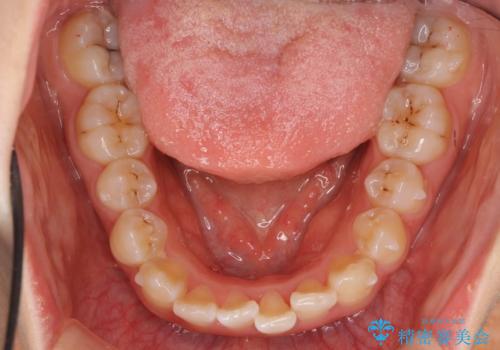

上下の前歯のがたつき 歯を抜かずに矯正

- 上下の前歯のがたつきを主訴に来院。

歯を抜かずに前歯を揃えています。

奥歯を後ろに下げたりなどはしていません。

奥歯を外に広げ、前歯中心に歯を少し削っていますが、健康には問題ない範囲で行なっています。